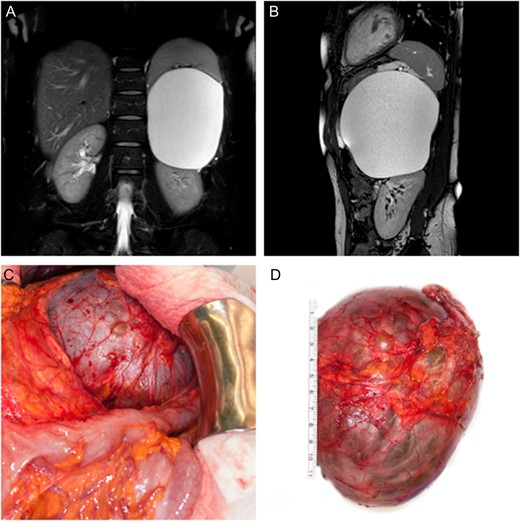

On physical examination, the patient had normal vital signs. Her abdomen was soft, non-tender and non-distended. Laboratory investigations showed a slightly elevated white blood cell count as well as C-reactive protein level. Beta-HCG test was negative. Computed tomography scanning of the pulmonary arteries was performed in order to rule out pulmonary embolism. The simultaneous display of the upper abdomen revealed a big cystic lesion, which seemed to be attached to the left kidney. Biochemical analysis and hormone testing showed no signs of a hyper functioning mass. Abdominal MRI revealed a maximum diameter of 12.5 cm. The origin of the cystic lesion was suspected either in the mesentery or the omentum majus (Fig. 1A and B). Considering the abdominal symptoms as well as the fact that neither origin nor dignity could be determined in this patient, a total surgical removal followed by histological examination was indicated.

We performed an upper midline laparotomy. To ensure a good anatomical overview, mobilization of the left colonic flexure was necessary and the omental bursa was entered. The distal part of the pancreas showed close proximity to the cystic lesion and needed careful separation. After adhesiolysis between the splenic surface, the posterior gastric wall as well as the parietal peritoneum, the left adrenal gland with its associated vein, was found to be the origin of the cystic tumor. Hence total adrenalectomy was performed in order to remove the intact cystic lesion (Fig. 1C and D). Following a short period of postoperative nausea and vomiting, gradual return to a normal diet was possible. The patient was discharged on the sixth postoperative day.

(A, B) Coronal and sagittal T2 weighted, fat suppressed MR image of the abdomen showing displacement of the spleen as well as the left kidney by the adrenal tumor. (C) Intra-operative finding showing close proximity of the cystic lesion to the left colonic flexure. (D) Surgically excised cystic tumor together with the left adrenal gland.